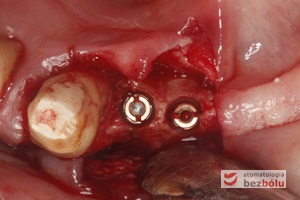

Wprowadzenie 4 implantów w odcinku przednim żuchwy